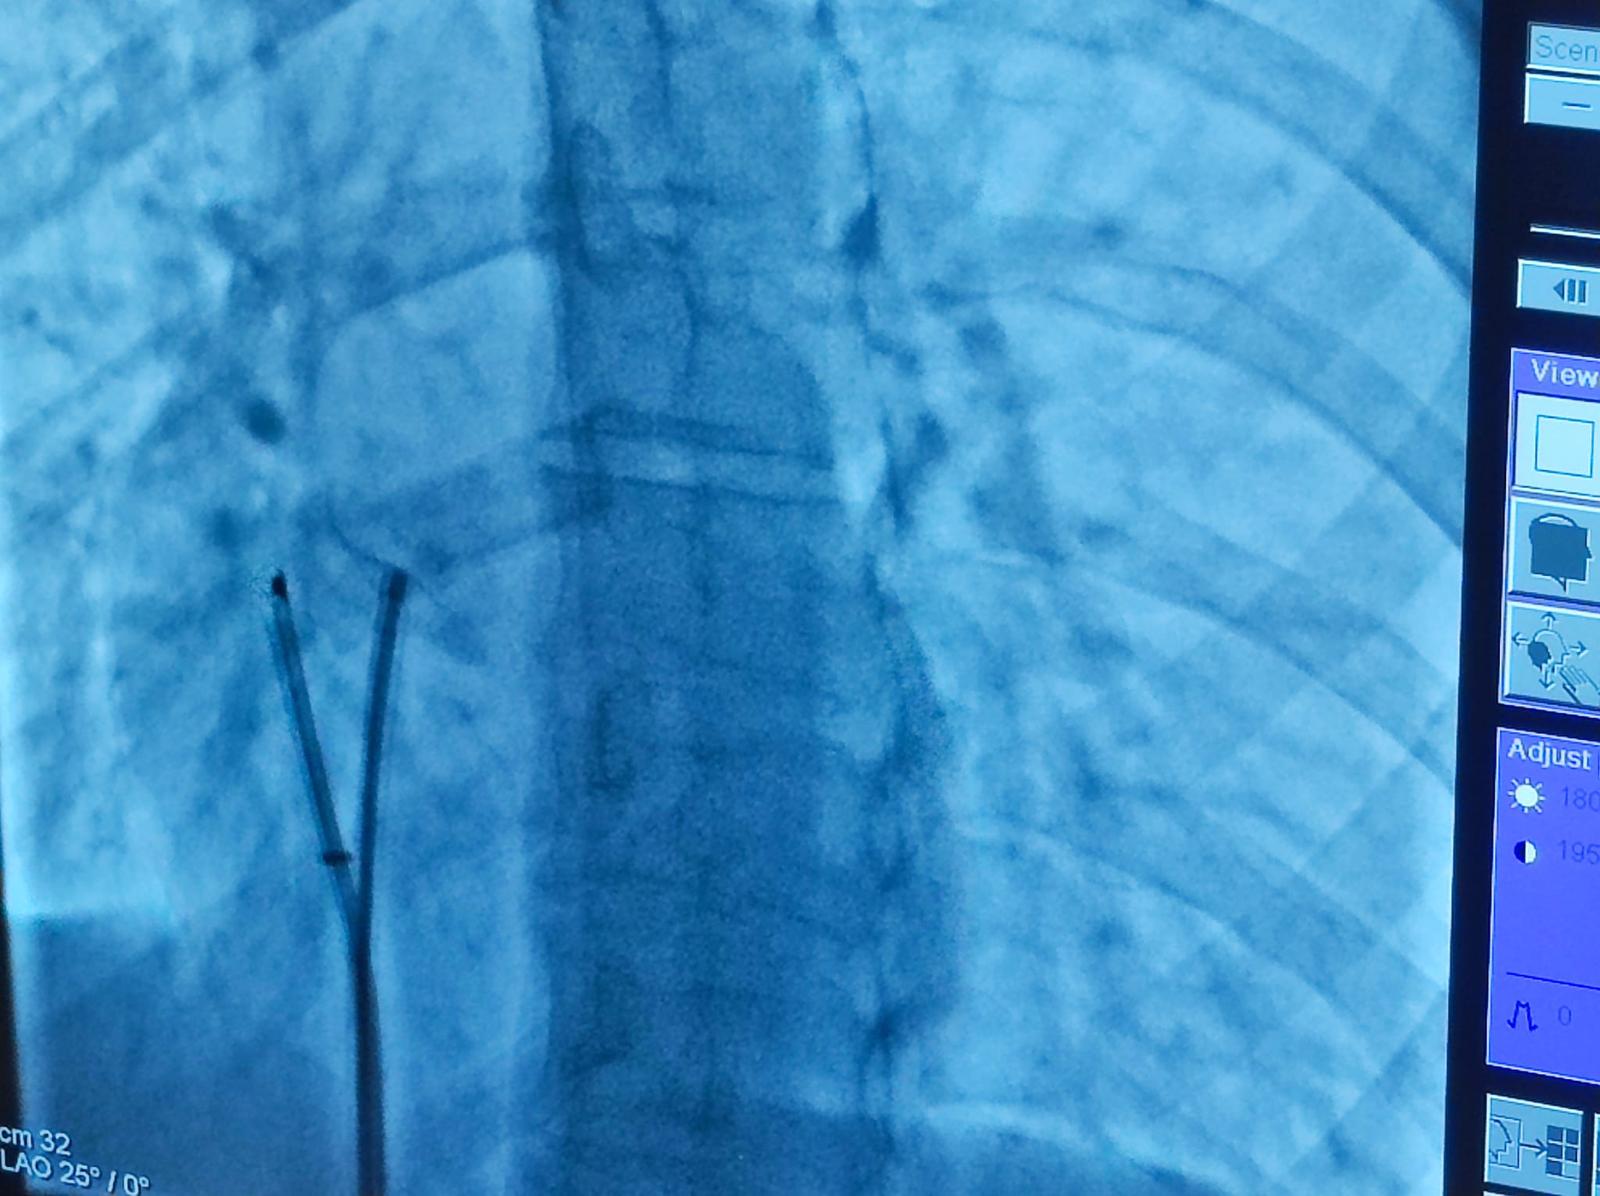

Nel corso della seduta sono stati eseguiti, con pieno successo, numerosi interventi di chiusura percutanea di vizi cardiaci congeniti, con tecniche percutanee mininvasive tra cui monitoraggio ecocardiografico intracardiaco, in pazienti di età compresa dai 20 ai 52 anni, provenienti sia dal territorio che da fuori regione.